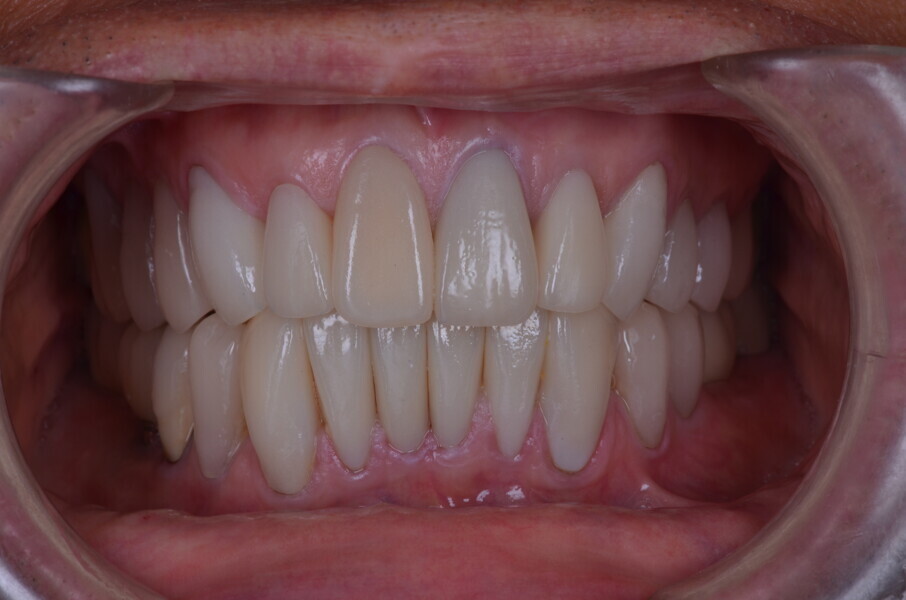

Figure 26 Closed mouth post op